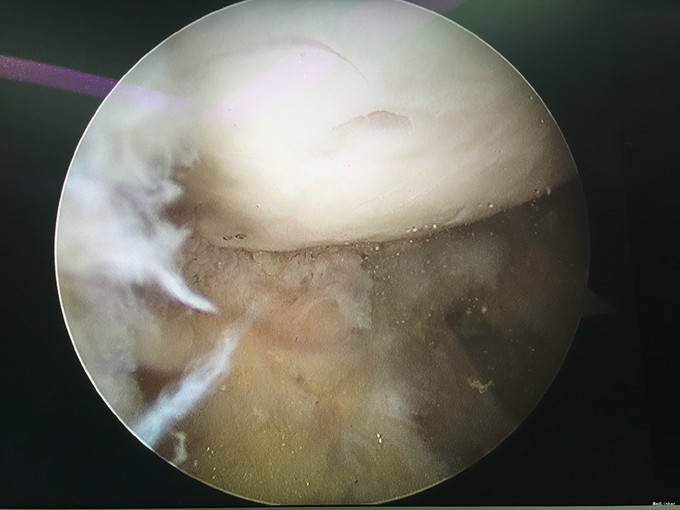

诊断:类风湿性关节炎 治疗:右膝关节镜下清理

随访:患者术后早期术膝肿胀消除明显,活动度较术前明显改善。患者继续至风湿免疫科行内科治疗。 讨论:对风湿性疾病的局部症状治疗,关节镜手术治疗不失为一实用而又有效的治疗方法。